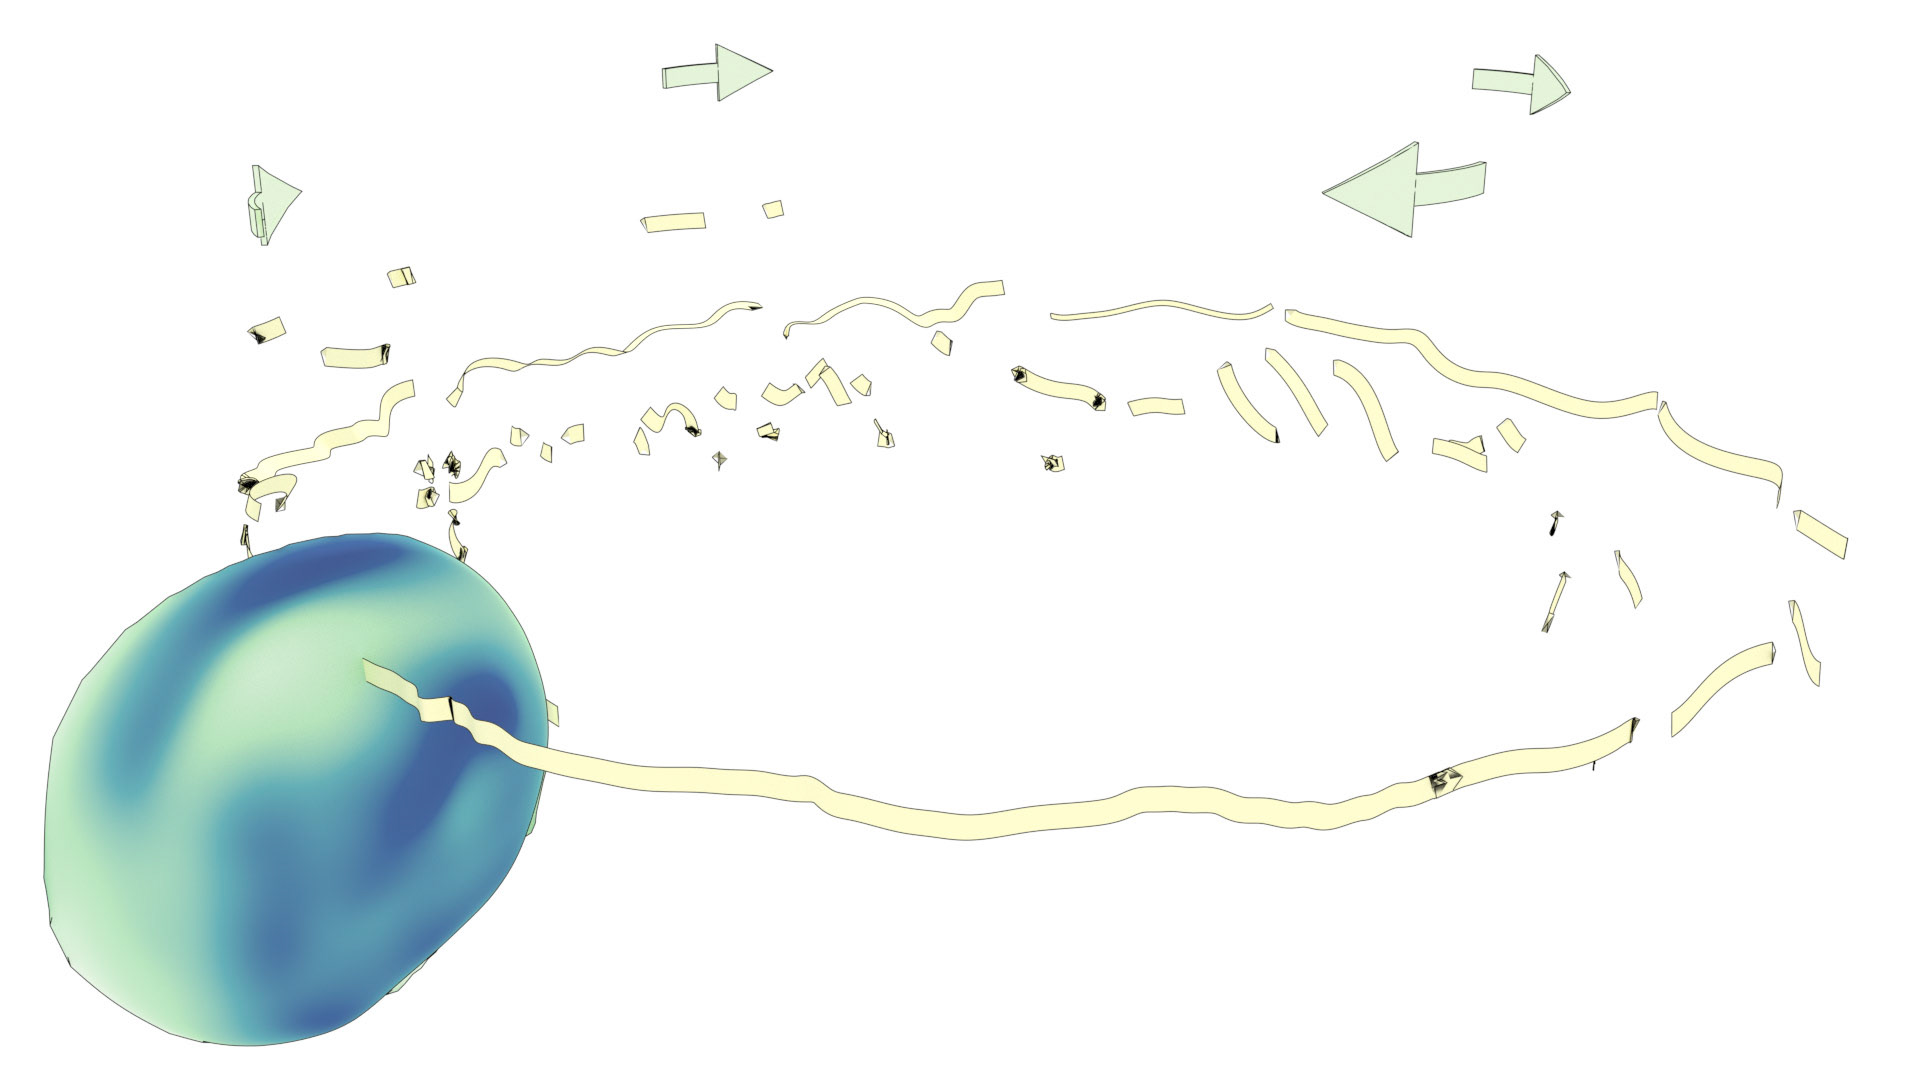

An ongoing collaboration with the Biomedical Simulation Lab (BSL), University of Toronto. In my role, I develop concept sketches and renderings that are then implemented algorithmically. The overall approach is to show turbulent flow visualizations without animation my mapping the transitions among states to carousel that corresponds to the cardiac cycle.